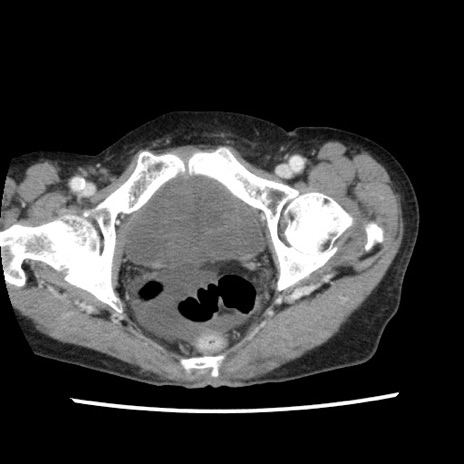

矢状断像